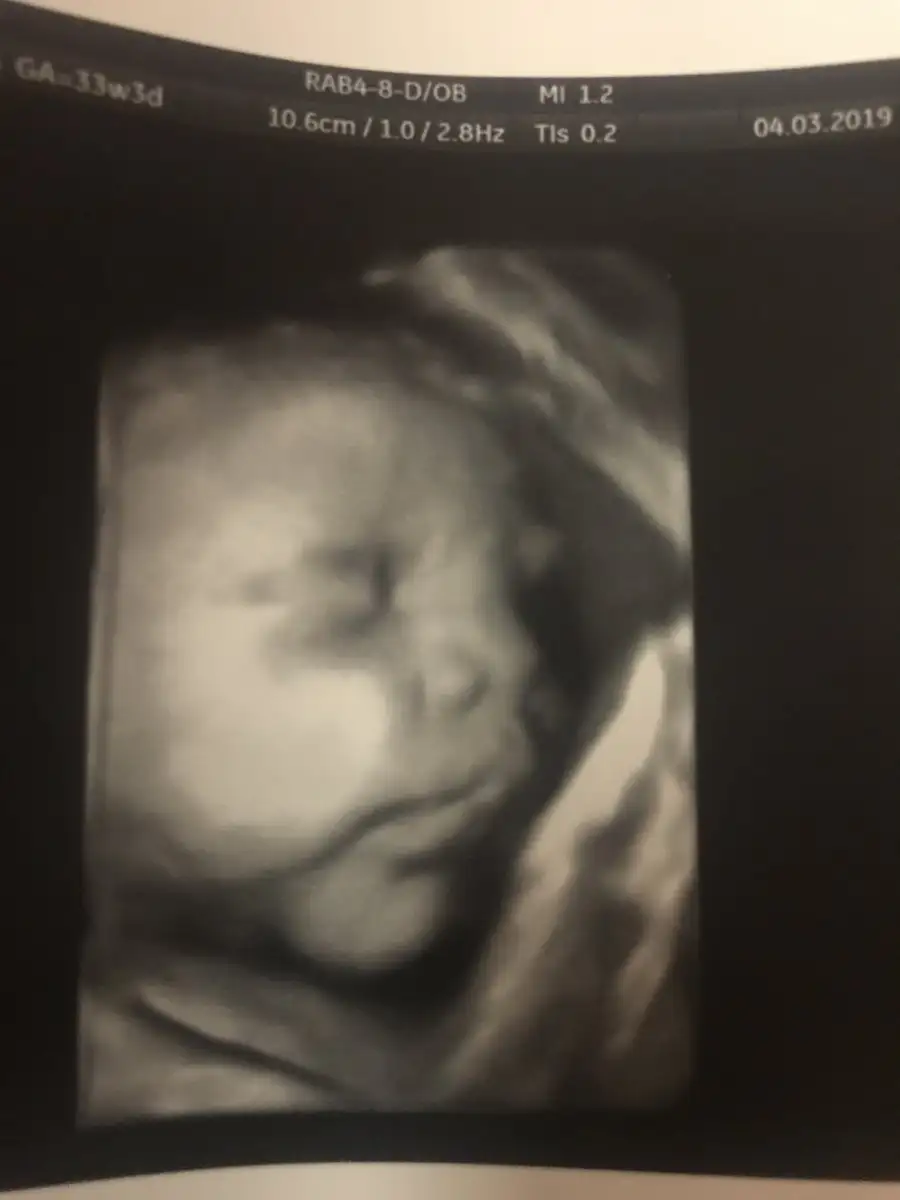

Oturdum şimdi yeni geldim iştenGeçenlerde bana da olmuştu canım gerçi sen tecrubelisin 2. Hamileliğin doğum sancısı olabilmesi için örneğin yarım saat boyunca 5 dk bir o kasılmanın olması gerekiyormuş mutlaka otur dinlen kuzu